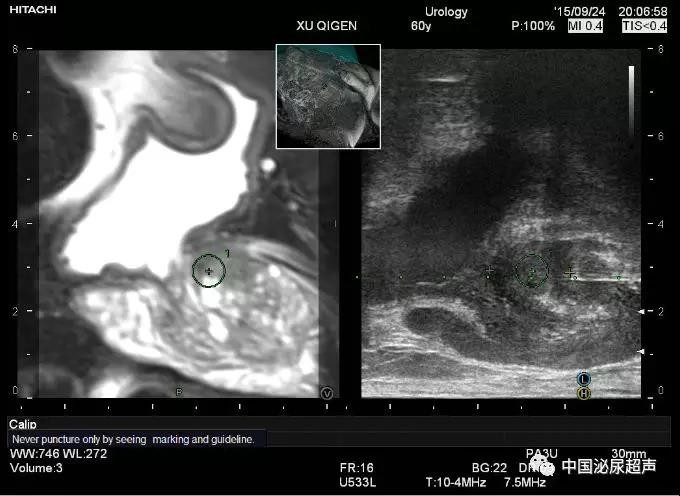

該研究的患者人群為首次進行前列腺活檢的男性。對有MRI可見損傷的患者隊列(定義為前列腺成像報告和數(shù)據(jù)系統(tǒng)第2版分數(shù)?≥?3),使用三種方法進行活檢,包括系統(tǒng)性活檢,認知融合MRI損傷靶向活檢以及軟件融合MRI損傷靶向活檢。另一組無MRI可見損傷的患者隊列,進行系統(tǒng)活檢以確定MRI方法的假陰性率。